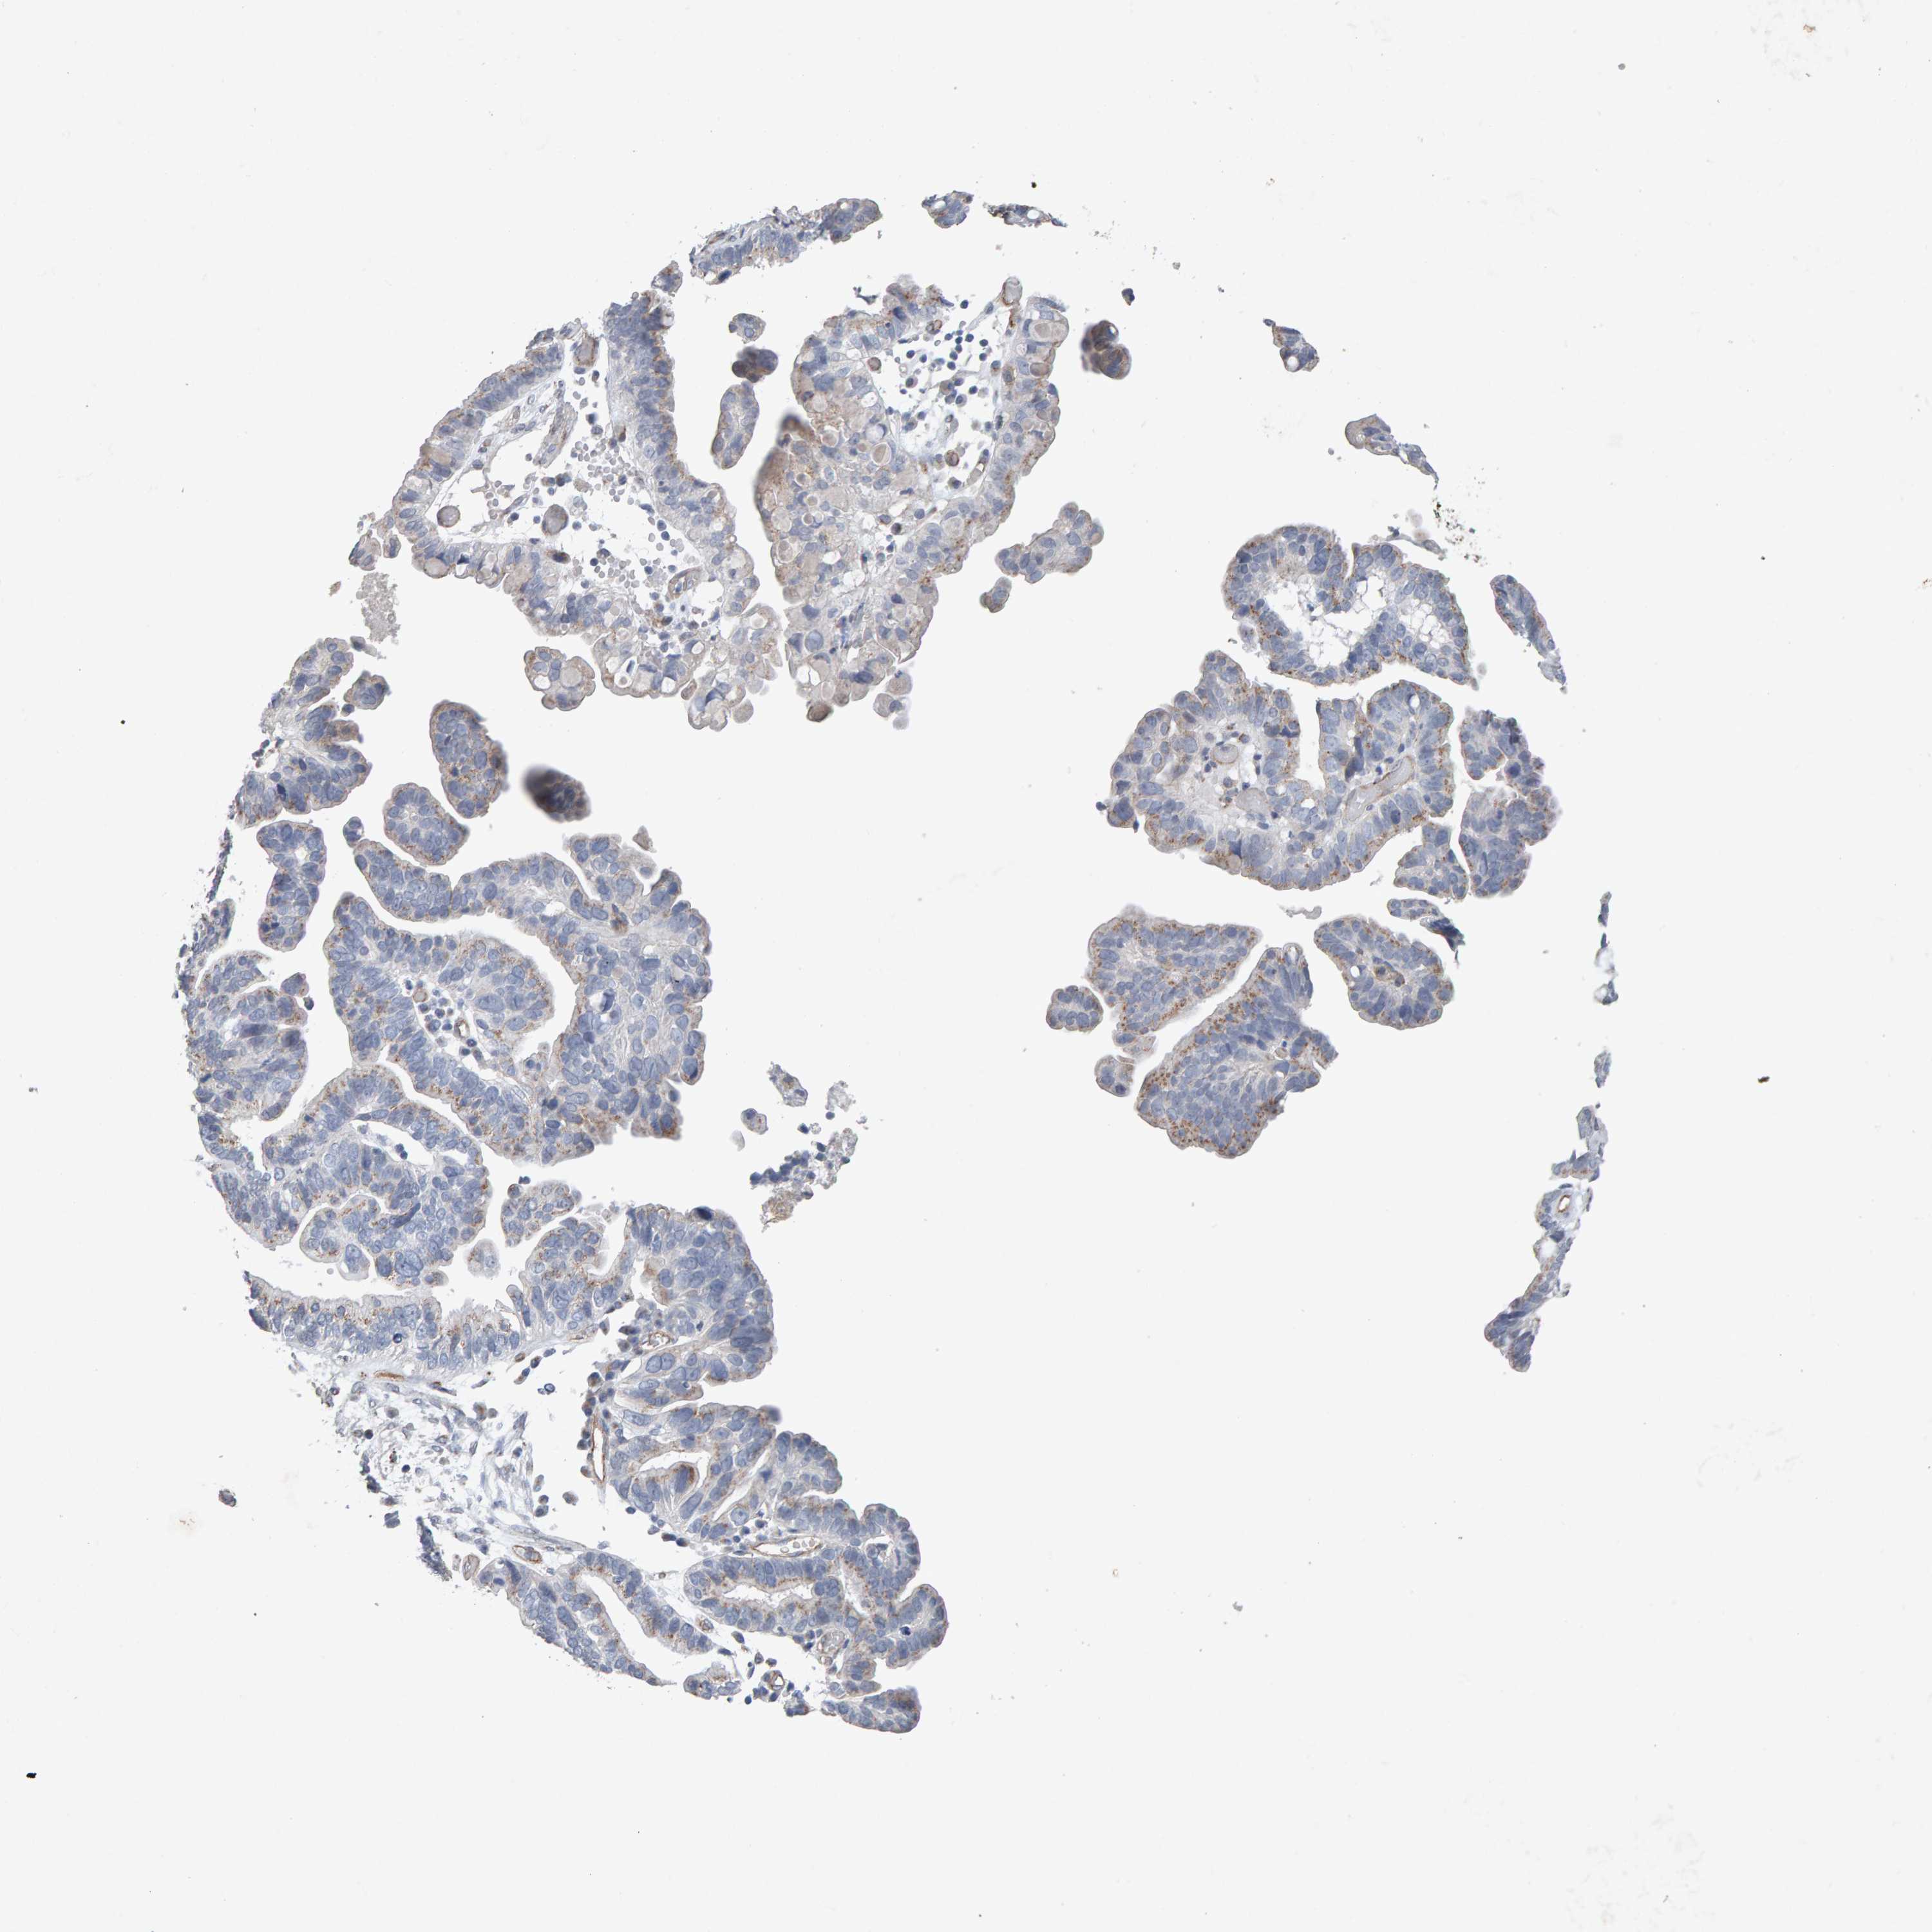

OVARIAN CANCER - Protein expressioni

A mouse-over function shows sample information and annotation data. Click on an image to view it in a full screen mode. Samples can be filtered based on level of antibody staining by selecting one or several of the following categories: high, medium, low and not detected. The assay and annotation is described here.

Note that samples used for immunohistochemistry by the Human Protein Atlas do not correspond to samples in the TCGA dataset.

Antibody stainingi

Antibody staining in the annotated cell types in the current human tissue is reported as not detected, low, medium, or high, based on conventional immunohistochemistry profiling in selected tissues. This score is based on the combination of the staining intensity and fraction of stained cells.

Each image is clickable and will lead to virtual microscopy that enables deeper exploration of all samples and also displays staining intensity scores, fraction scores and subcellular localization as well as patient and tissue information for each sample.

Antibody CAB022442

Antibody CAB022443

Carcinoma, endometroid

Cystadenocarcinoma, serous, NOS

Cystadenocarcinoma, mucinous, NOS

Carcinoma, NOS